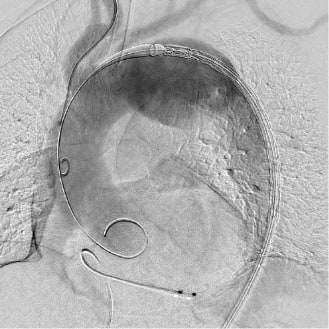

ハイブリッド手術室とは、手術台にX線血管撮影装置を組み合わせた手術室のことです。従来の手術に加えて血管カテーテル室で行われていた治療を組み合わせることにより、最適な治療を行うことが可能なシステムです。

当施設では、X線血管撮影装置としてフィリップス社製「Azurion7 C20 with FlexArm」を導入し、ハイブリッド手術室を構築しました。手術室と同じクリーン度を有しており、様々な手術に対応可能です。

大動脈手術では、このシステムを利用して積極的に低侵襲治療である血管内治療(ステントグラフト内挿術)を行っています。腹部大動脈瘤だけではなく、弓部に至る胸部大動脈瘤でも、外科的処置を併用したステントグラフト治療を行なっております。